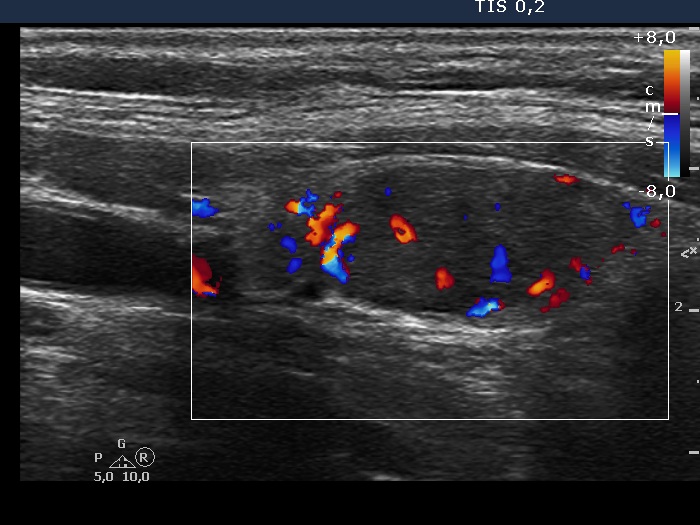

Thyroid cancers - case 1202 (ultrasonographic picture 4)

Right lobe, longitudinal scan, color Doppler mode. The nodule has intranodular vascularity and presents signs of perinodular blood flow as well.